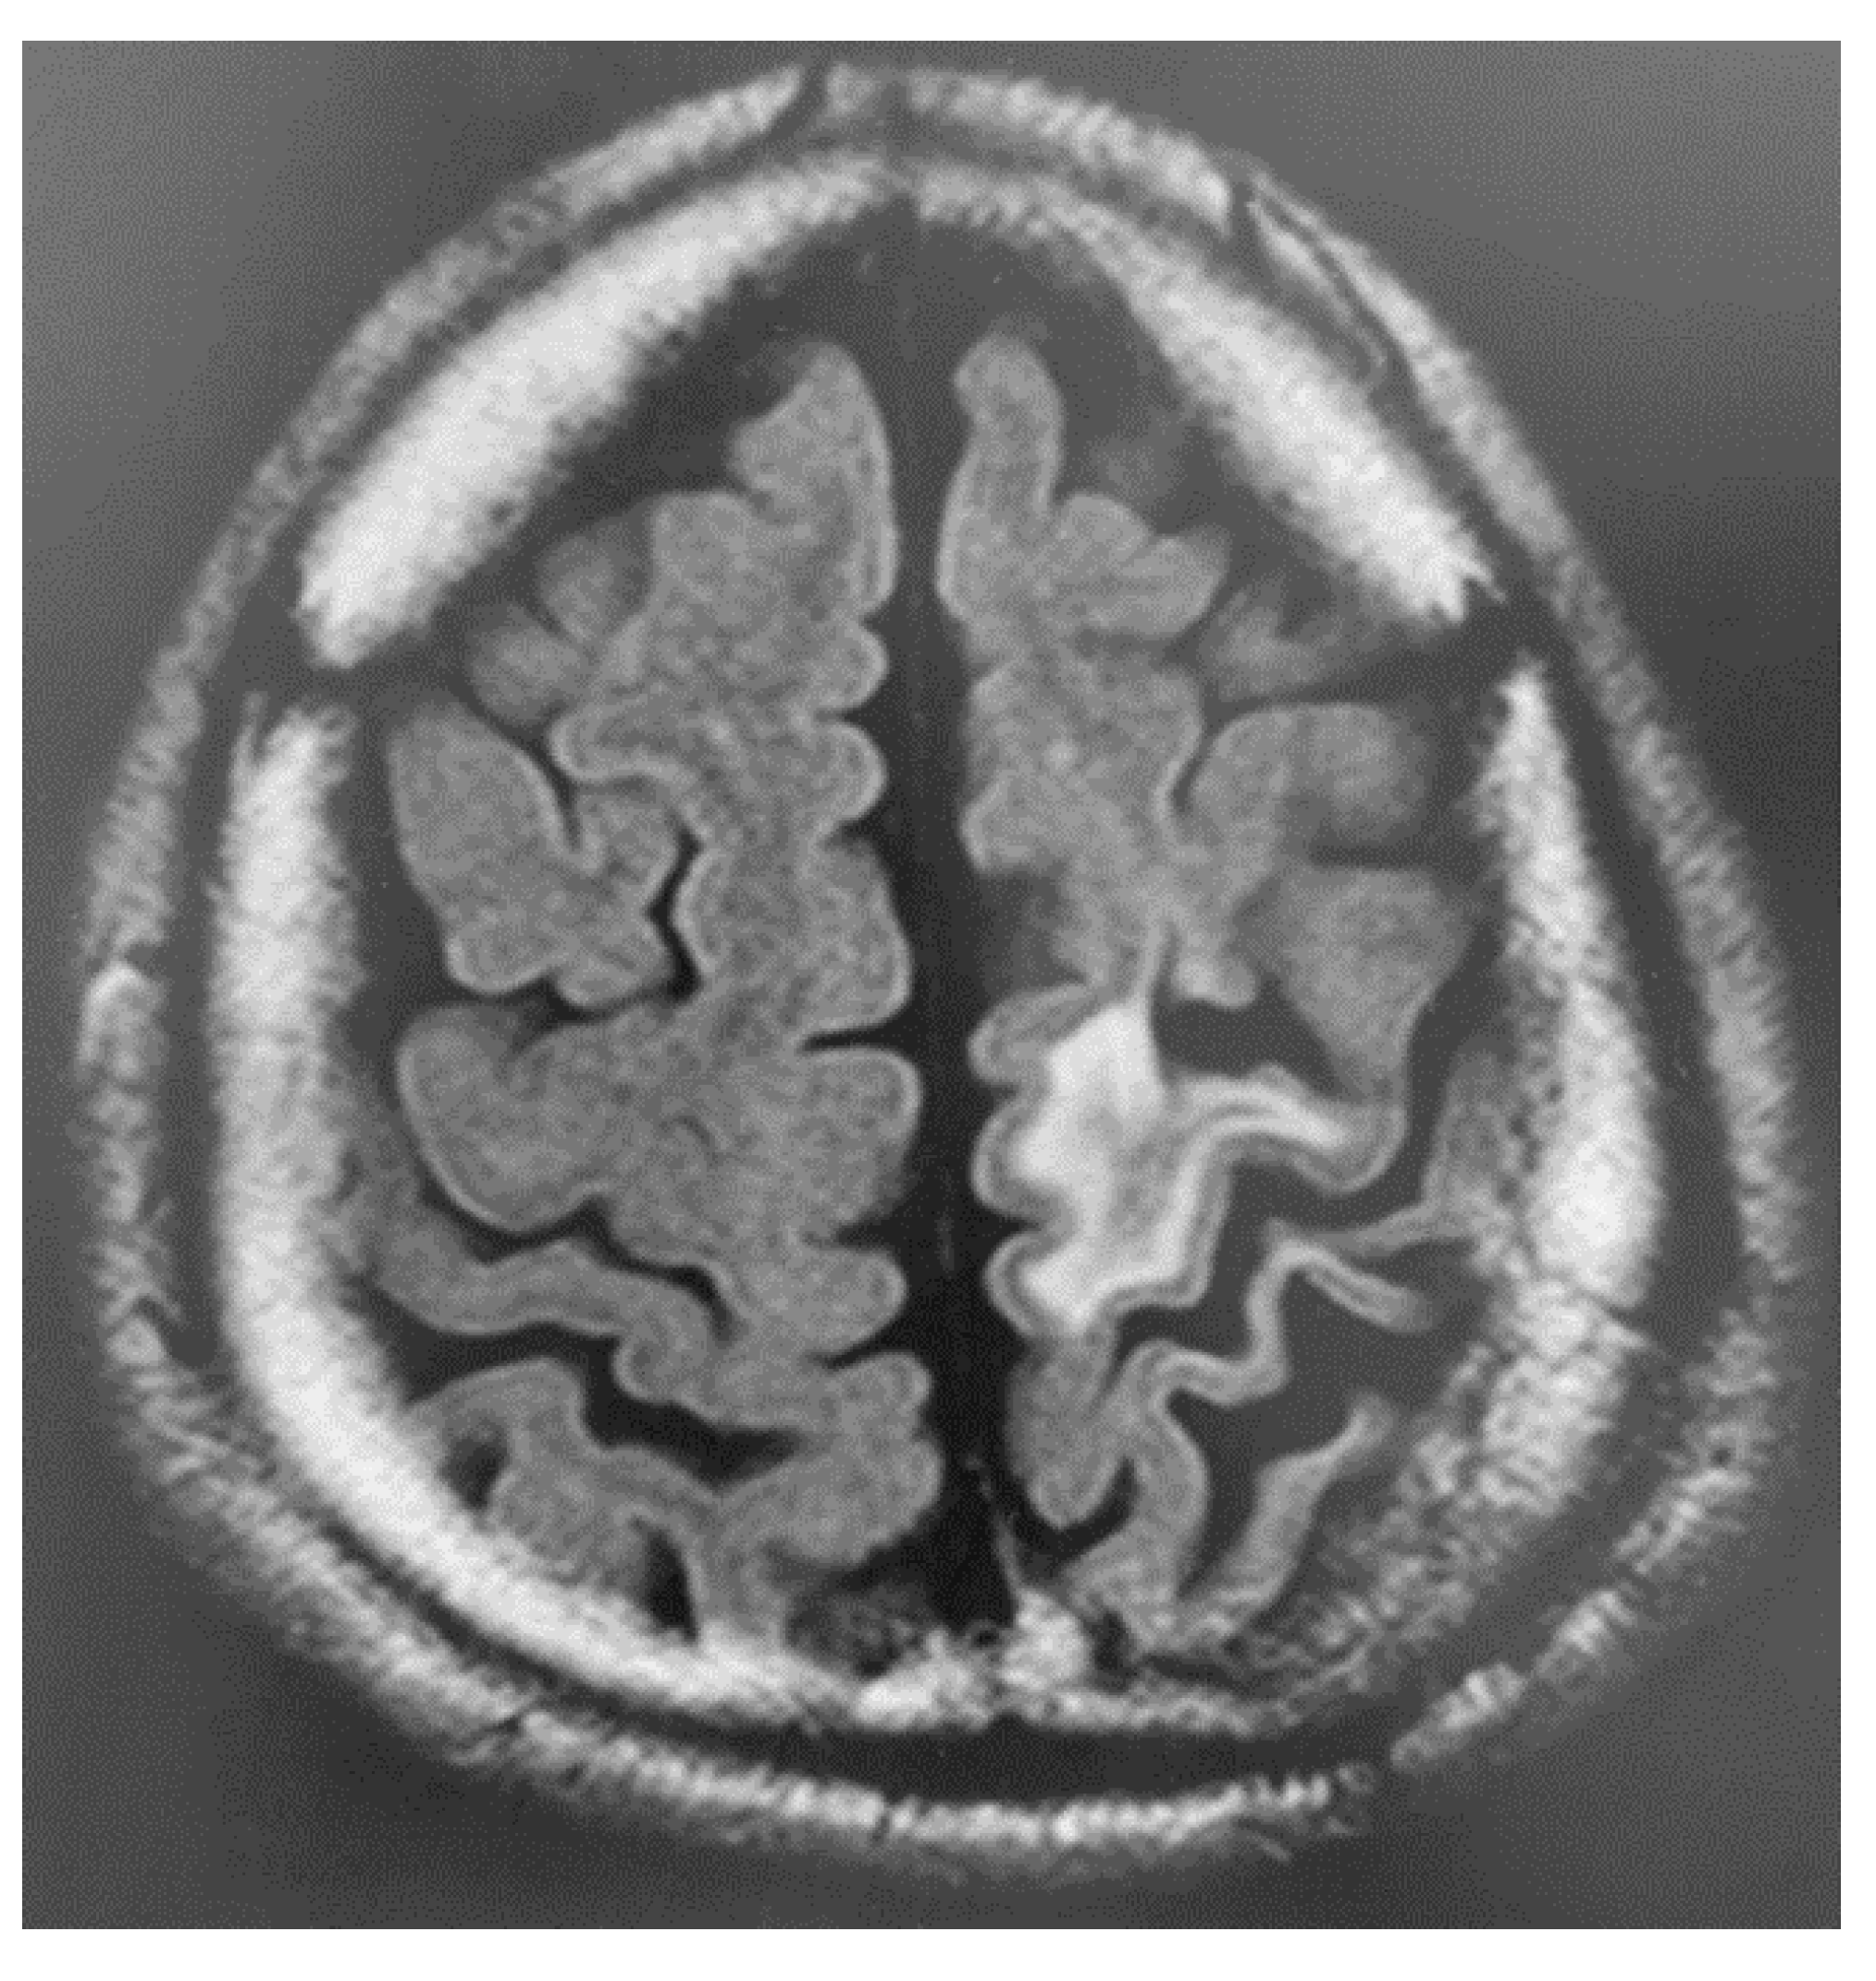

3. Instruments Used for Brain Imaging